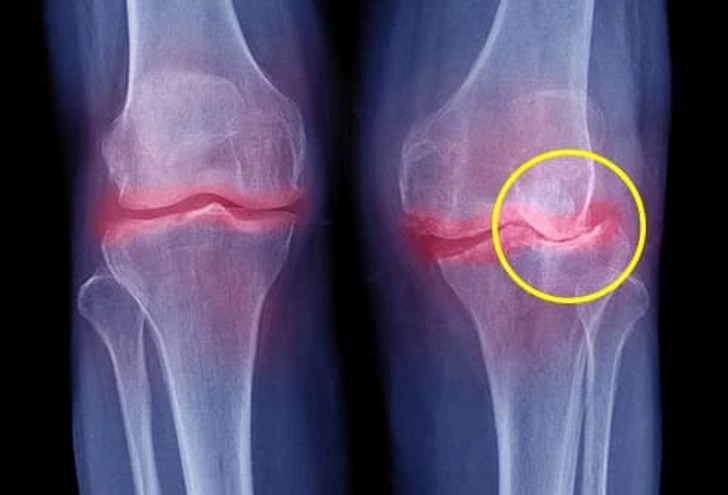

As we age, the wear and tear on our joints becomes more noticeable. Conditions like osteoarthritis, past injuries, repetitive stress on certain joints, or autoimmune disorders such as rheumatoid arthritis can all contribute to chronic joint discomfort. This often leads to reduced mobility and a more sedentary lifestyle, which can worsen symptoms.